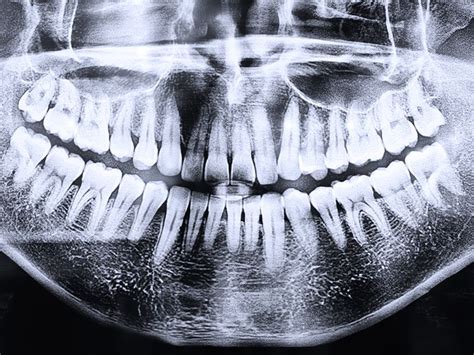

Pruebas de diagnóstico

Contratar un seguro dental te permite contar con todas las pruebas necesarias para comprobar el estado de tu salud bucodental y llevar a cabo los tratamientos necesarios. Según la póliza que elijas, podrás contar con radiografías o TAC dental. Este tipo de diagnósticos, ayudan a estudiar correctamente el estado de tus dientes y encías para comprobar su estado y saber los procedimientos que es necesario realizar.

| Radiografías | Diagnóstico por imágenes para detectar problemas ocultos. | Según necesidad, algunas incluidas sin coste. |